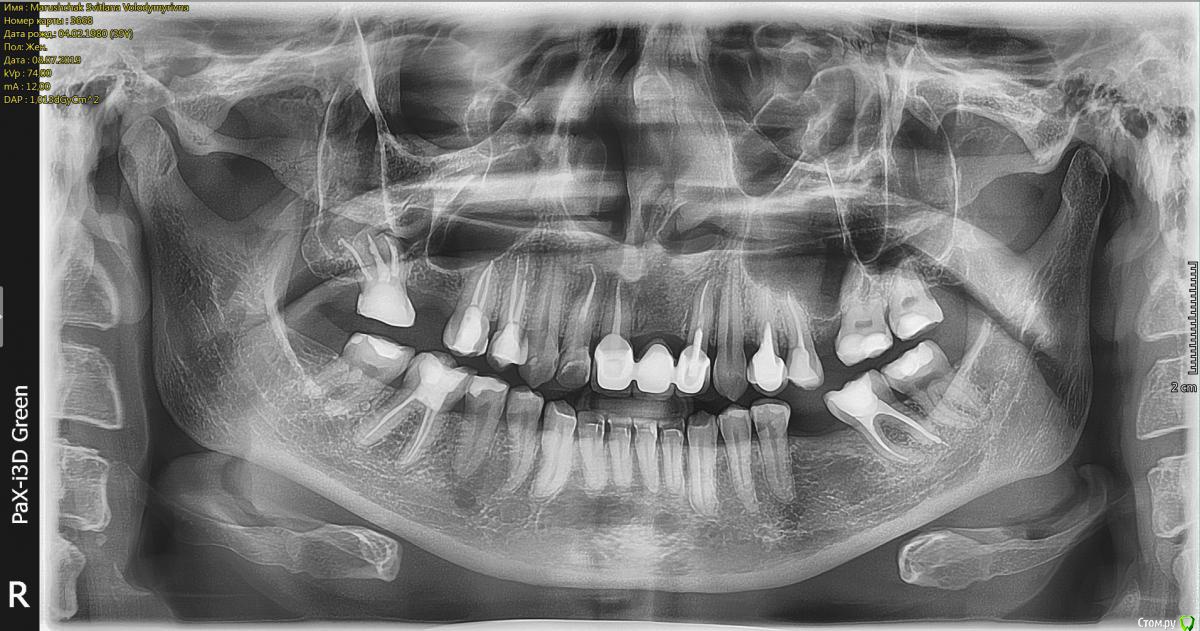

сирена Опубликовано 12 июля, 2019 Поделиться Опубликовано 12 июля, 2019 Нет там никакого периодонтита пятого зуба.Все зубы пролечены хорошо. 1 Ссылка на комментарий